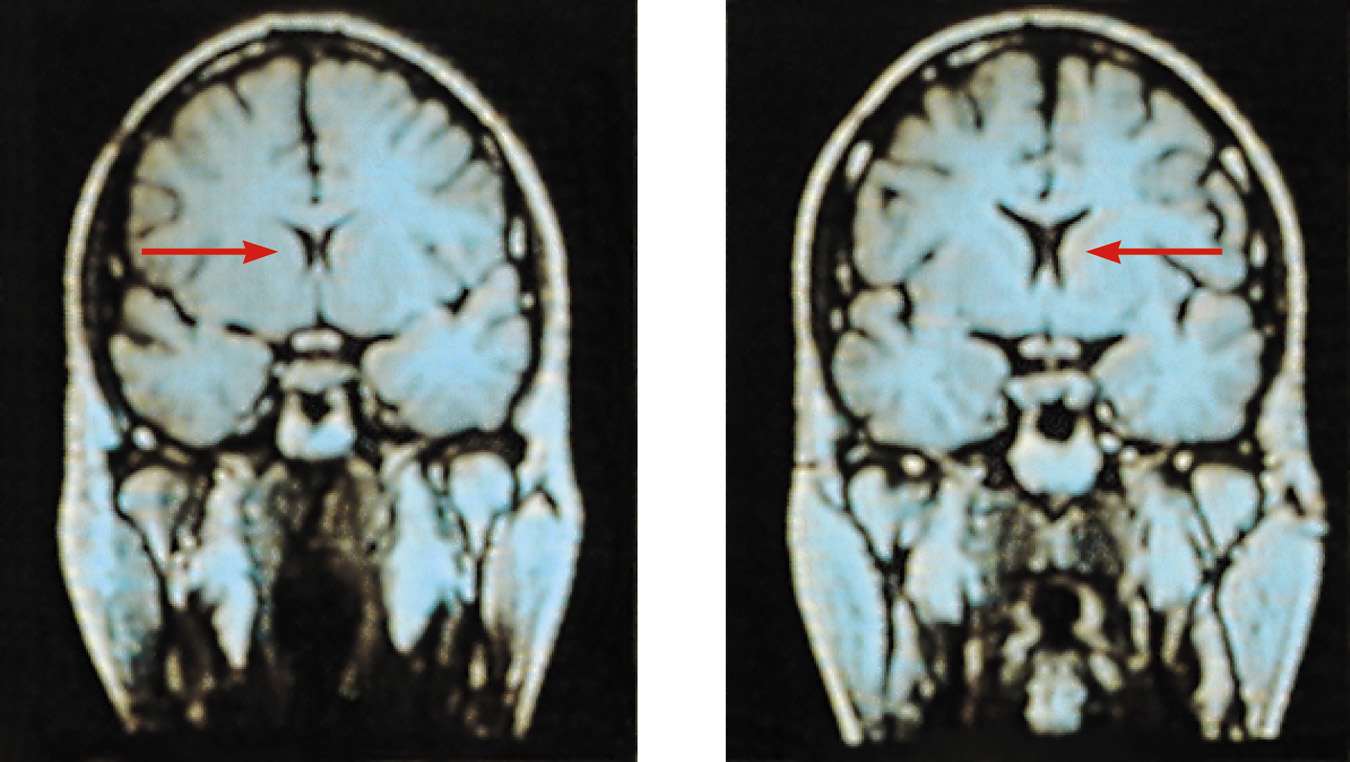

Schizophrenia

• If depression is the common cold of psychological disorders schizophrenia is the cancer.

Chronic and Acute Schizophrenia

• When schizophrenia is slow to develop (chronic/process) recovery is doubtful. Such schizophrenics usually displays negative symptoms.